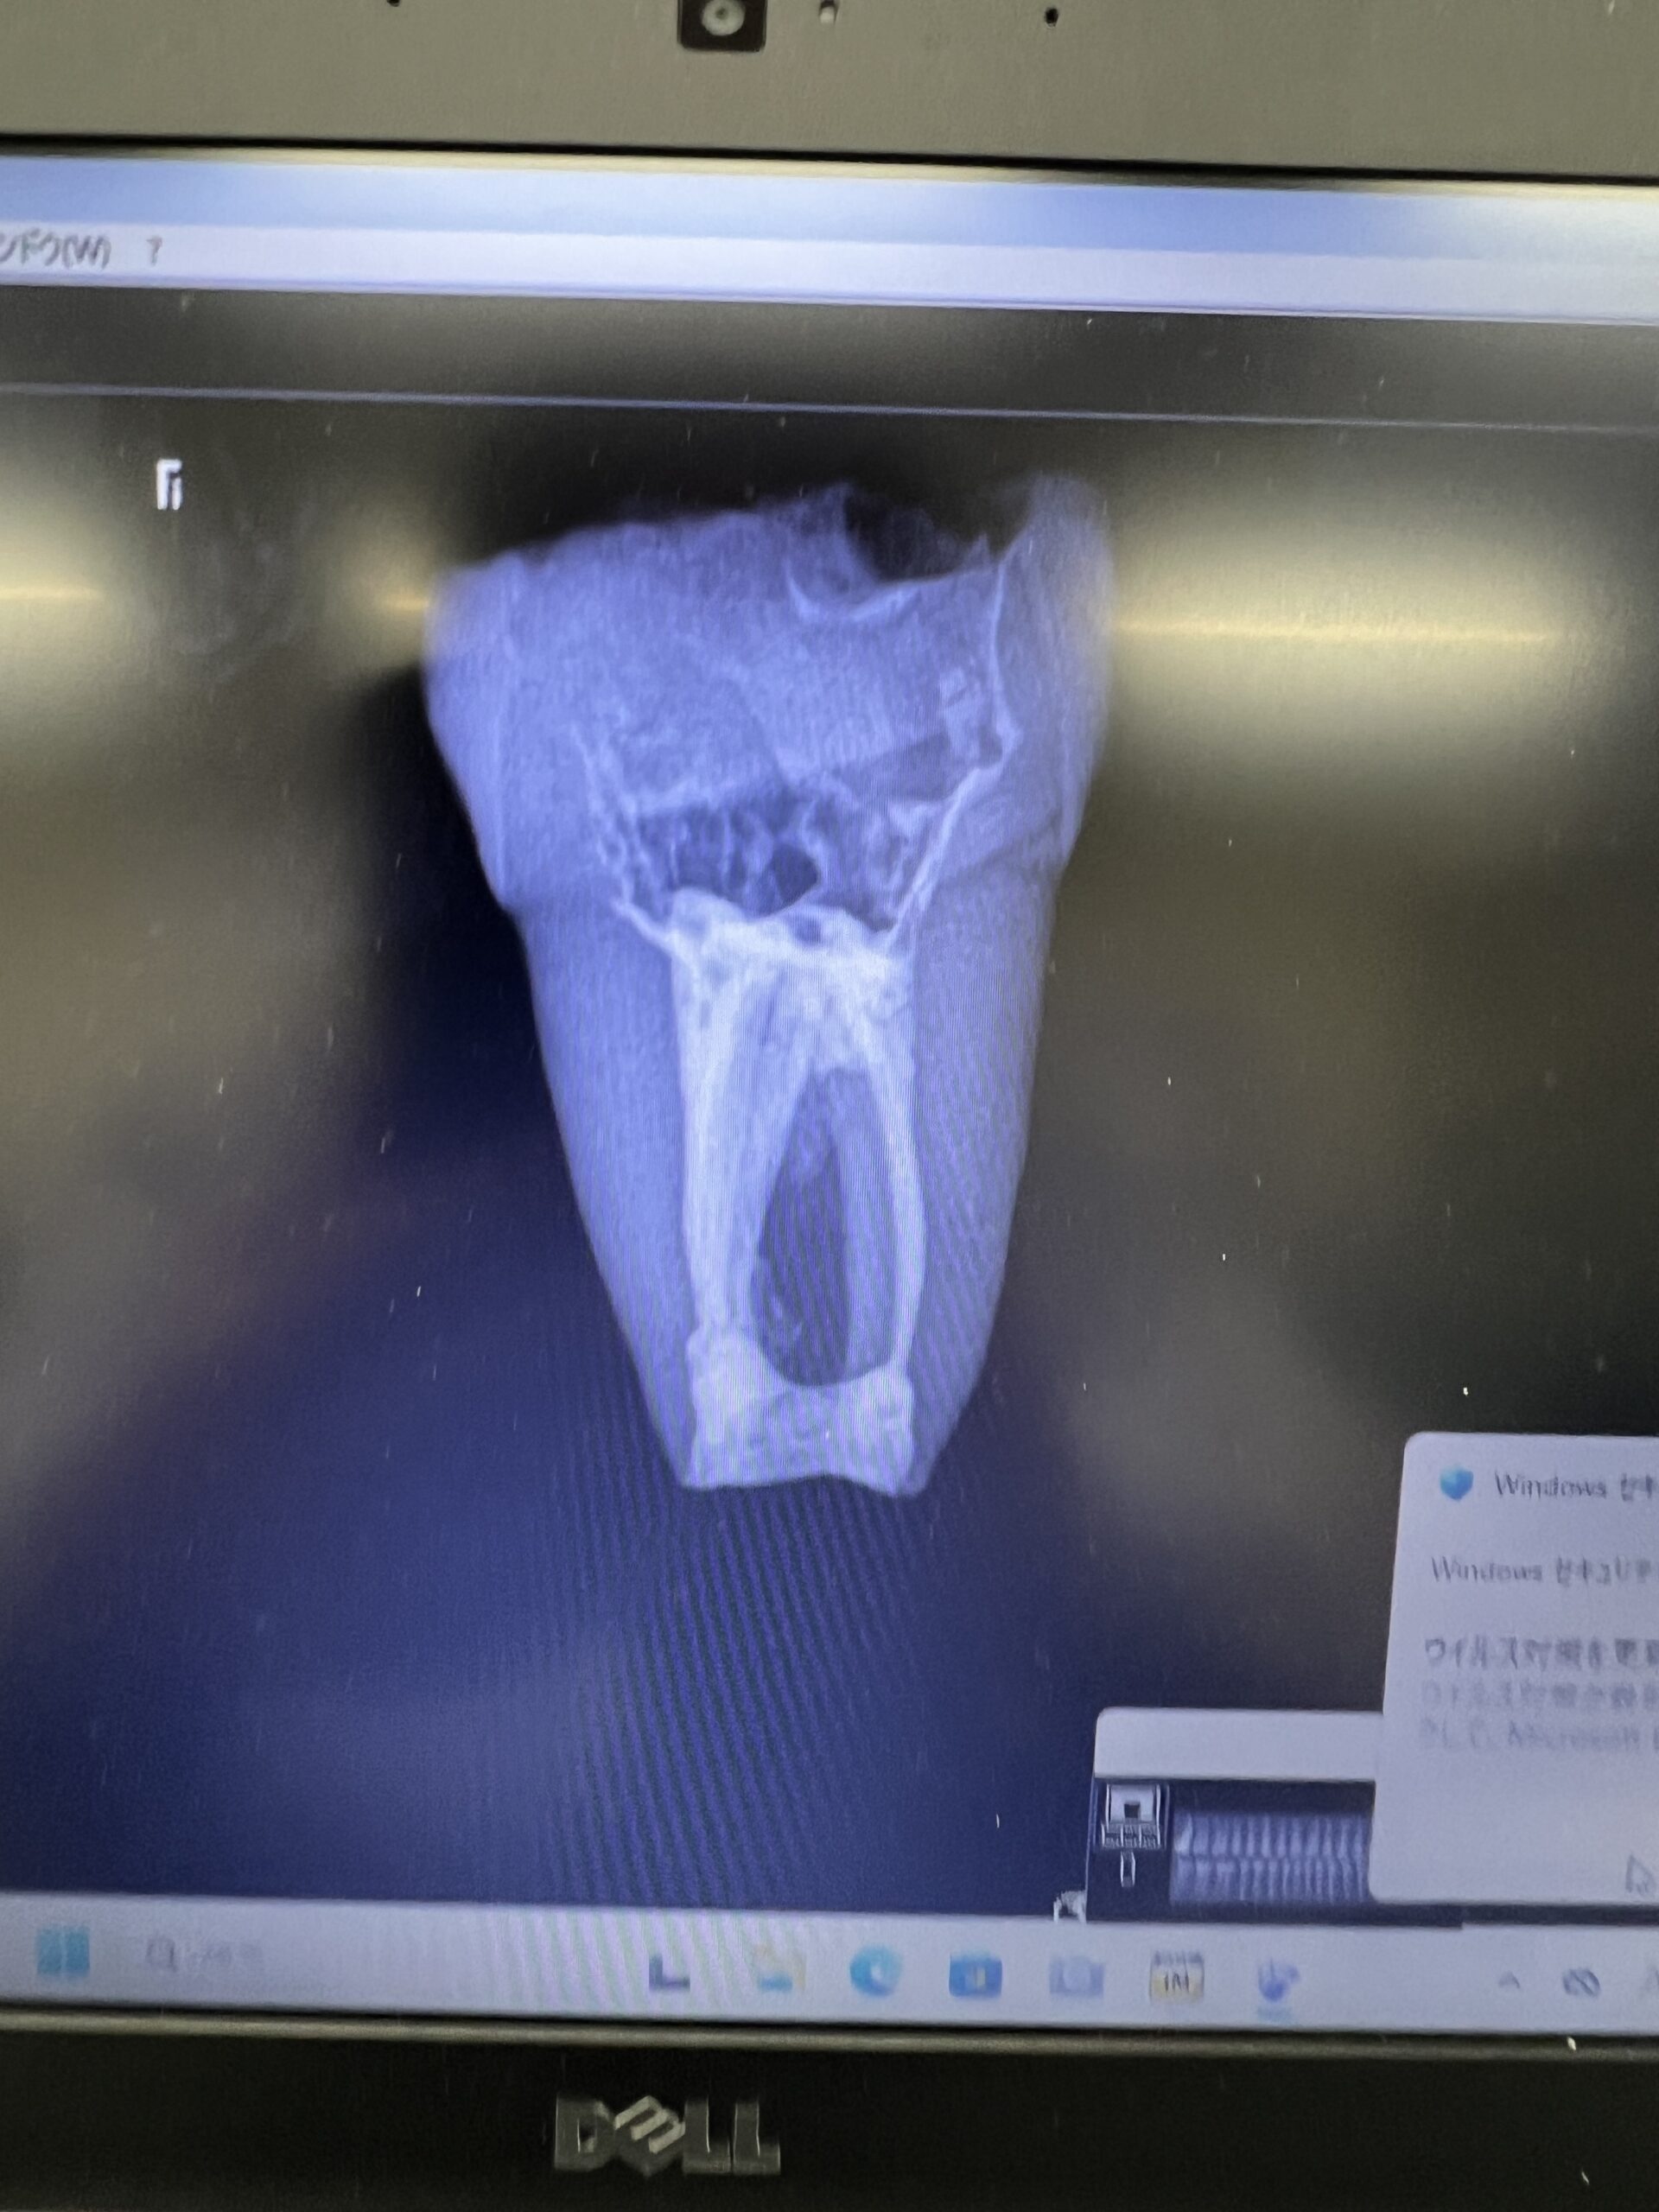

ここで、撮影をしてもらったCBCTを公開しよう。以下である。

これは私なら、もっと切断してやり直すだろう。

絵が、しょっぱいからだ。